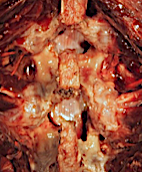

Visión cenital: lado izquierdo con abordaje interlaminar puro; lado derecho ampliado (sin dañar pars ni faceta significativamente)

En el nivel superior, se ha realizado un abordaje interlaminar puro (para descompresión del canal central). Obsérvese la integridad de las estructuras óseas.